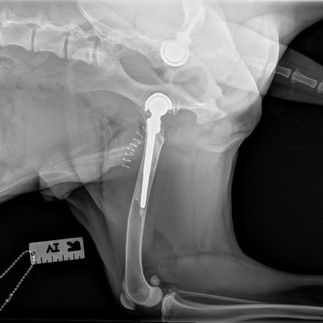

Post-Op X-Rays

1 Week Post-Op

January 23rd 2023

Today marks 1 week from Ducky’s right total hip replacement. We’ve spent a few days and all evenings resting at home, while other days were spent recovering at work with me.